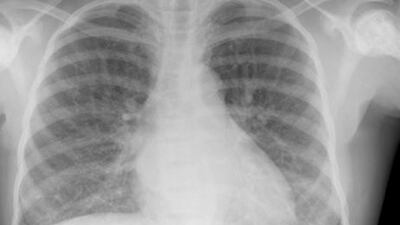

Typical findings on a chest X-ray in sickle cell disease, show a slightly enlarged heart. iStockphoto